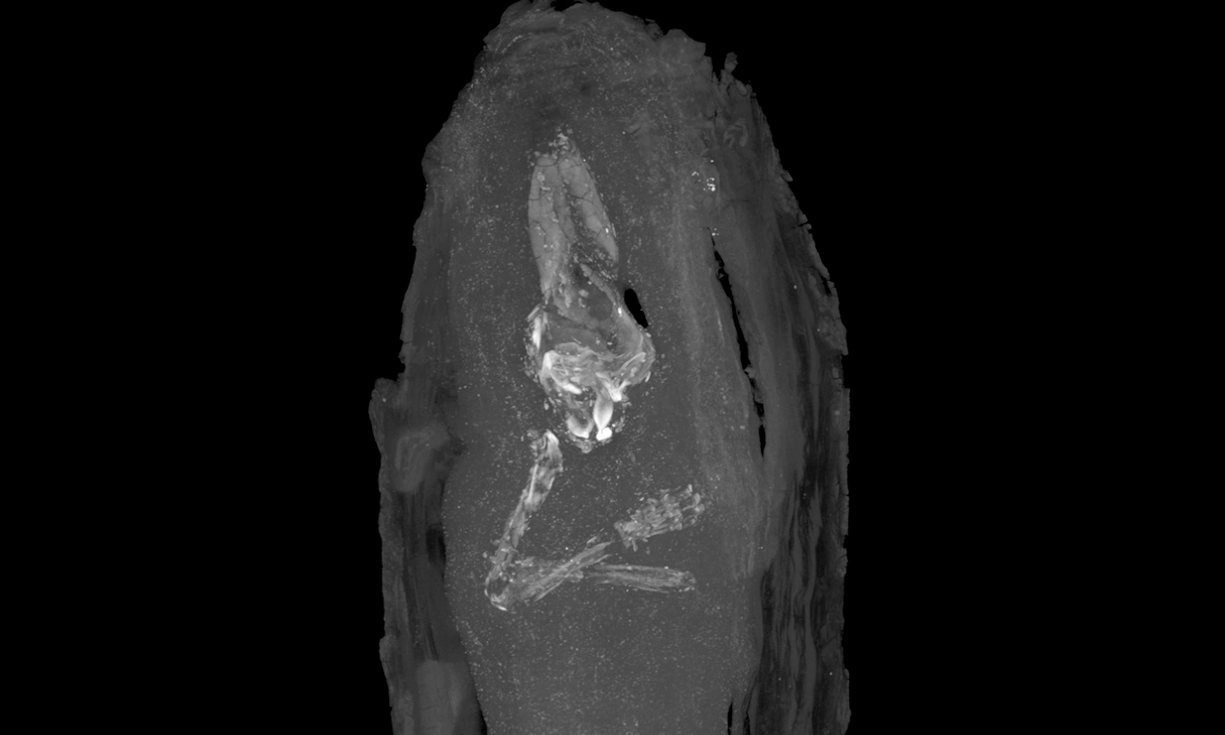

Egiptologii din cadrul muzeului au încercat să afle ce se găseşte în interiorul sarcofagului folosind raze X, însă rezultatele au fost neconcludente. Prin urmare, specialiştii au decis să efectueze noi analize, la Departamentul de Zoologie din cadrul Universităţii din Cambridge, unde au putut folosi un tomograf performant.

Interpretând rezultatele analizelor, specialiştii au reuşit să determine vârsta pe care a avut-o fetusul atunci când a murit: între 16 şi 18 săptămâni. În ceea ce priveşte dimensiunile sarcofagului, acestea sunt similare cu cele ale unei cutii de pantofi.

Rezultatul scanării efectuate cu ajutorul tomografului (Foto:theguardian.com/Fitzwilliam Museum)